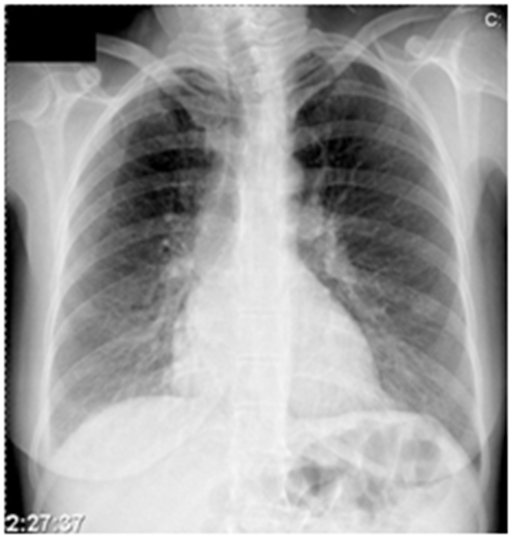

Clinically, all patients had symptoms of common infectious syndromes with fever 37.5 - 39.0C, malaise, headache, sore throat, pain in muscles and joints, and characteristic rashin the skin and mucous membranes of the oral cavity (Figure 1 A, B&C). Inflammation of the upper respiratory tract was founded all patients. Syndrome of angina, aphthous stomatitis and tonsilopharyngitis has been registering in all patients. Pneumonia is registered with 17 (58, 62%) patients, of which 14 (47%) cases were of primary interstitial pneumonia. Serious respiratory complications for mixed viral-bacterial infection (with participating Micoplasma pneumoniae, Chlamydia pneumoniae and Heamophilus influenza) in HFMD patients, is diagnosed in 3 (10, 34%) cases (Figure 2).

Figure 2 Primary interstitial pneumonia in our patients, were registered in 14cases, and serious respiratory complications for mixed viral-bacterial infection in 3 cases with HFMD.

To estimate the severity of pneumonia, we used clinical and laboratory parameters (age, presence of accompanying chronic infections, respiratory frequency, mental status, blood pressure, blood oxygen saturation, blood count and differential blood count), and microbiological findings. Investigations have shown that in 3 cases, the weight of pulmonary complications included mixed bacterial - viral pneumonia, with serological detection of co-infective participation of Chlamydia pneumonia, Micoplasma pneumoniae and Heamophilus influenza. Laboratory tests have shown that this severe cases are associated with total leukocyte count (>10-16 x 109), hyperglycemia, and raised level of CK-MB. These patients had a prolonged and difficult course of disease. Are treating in hospital and request antibiotic treatment. In the sample of 29 cases, with PCR method, it was confirmed participation of enteroviruses in 21 (72%) cases and in 8 (28 %) cases; we detected coxsackiaeviruses by ELISA method. Precise definition of viral serotypes was not possible due to the technical limitation of microbiological laboratory (Figure 2). Co-infective participation of bacterial agents in pulmonary complication was detecting by ELISA method.

Our investigations showed the participation of the children population (of school and pre-school ages) is dominant 20 cases. Adults participated with 9 cases. In total sample of cases with HFMD, the upper respiratory disturbances have registered in all patients. The primary interstitial pneumonia, was found in 14 (47%) of patients. Serious respiratory complications for mixed viral-bacterial infection has registered in 3 (10, 34%) of HFMD patients. In our cases, the most frequent are respiratory tract complications. Identify the clinical features of disease, and the application of rapid and appropriate symptomatic therapy and antibiotic therapy in mixed viral-bacterial pneumonia, are the reason why we did not even more difficult complications. Except the transient tachycardia associated with high fever, in our series were not registered weight cardiovascular and central nervous system (CNS) complications.